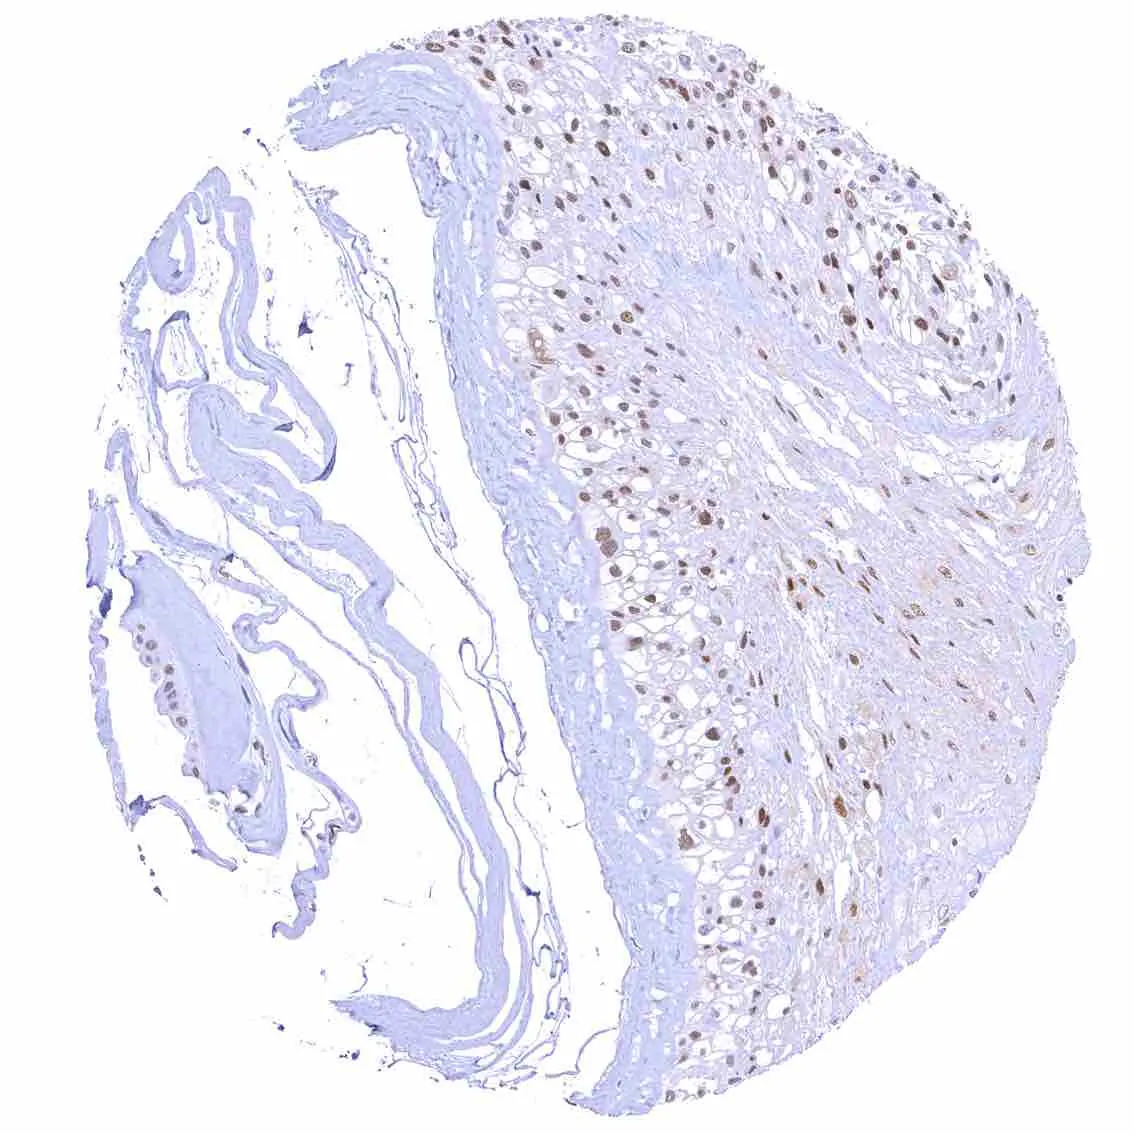

Esophagus, squamous epithelium – Nuclear staining of squamous epithelial cells predominates in the more mature cell layers (top 50_ of the epidermis).